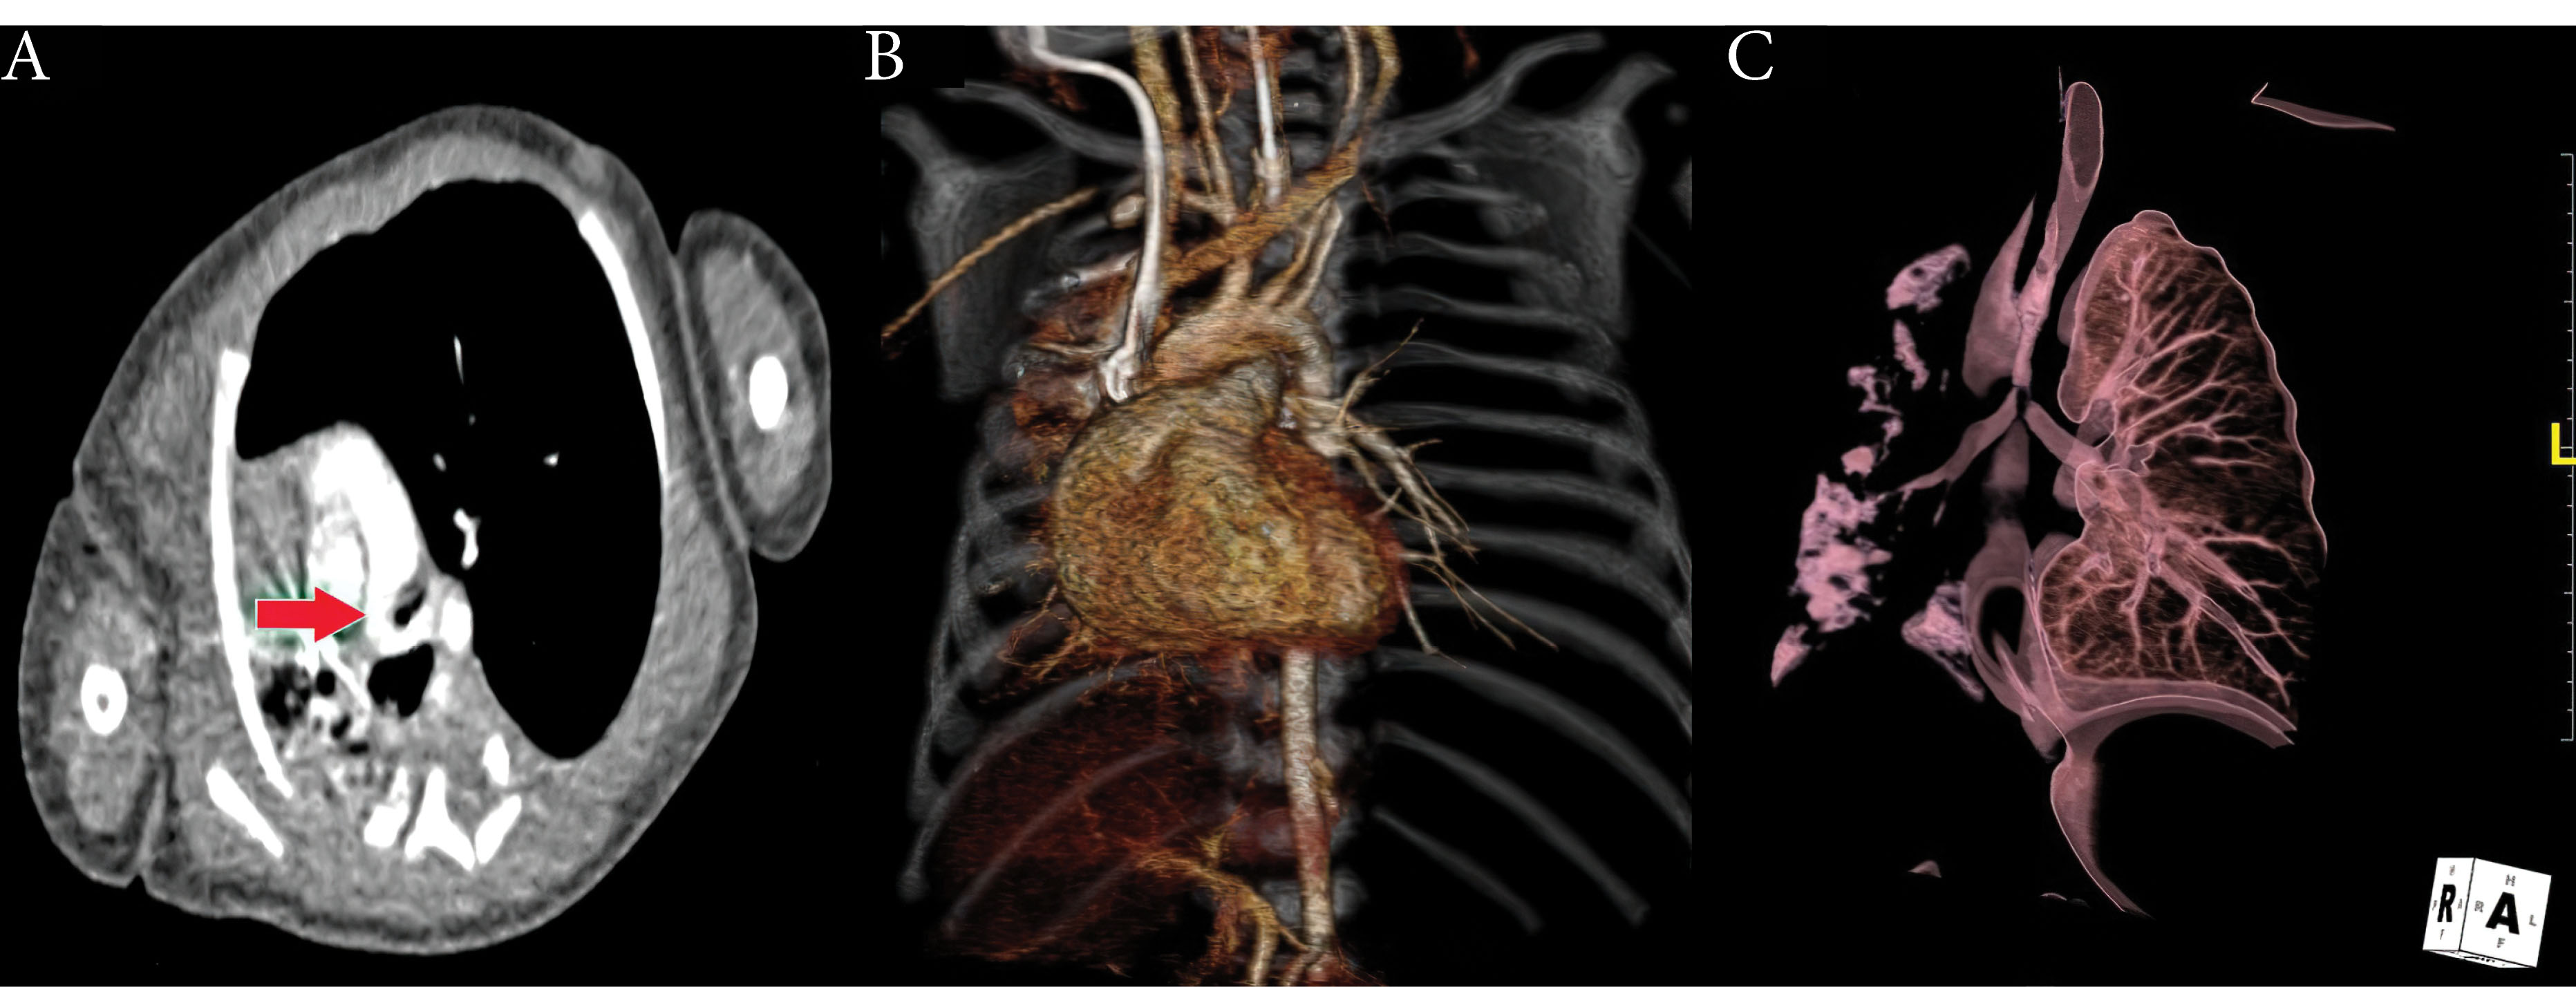

Figure 1.

Axial section of CT showing aberran course of the left pulmonary artery and narrowing of the tracheal bifurcation (Red arrow). B. 3D CT image showing the left pulmonary artery that not branch out from the pulmonary trunk. C. 3D CT image showing the narrowing of the tracheal bifurcation

Figure 3.

The postoperativecontrolCT images showing normal branches of the pulmonary trunk (arrowhead: left PA, black arrow: right PA).